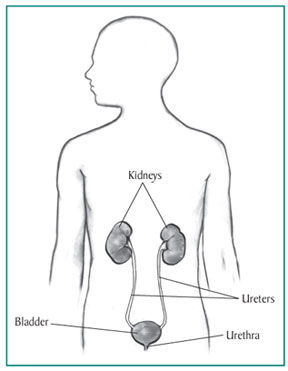

The kidneys are two bean-shaped organs, each about the size of a fist. They are located just below the rib cage, one on each side of the spine. Every day, the two kidneys filter about 120 to 150 quarts of blood to produce about 1 to 2 quarts of urine, composed of wastes and extra fluid. The urine flows from the kidneys to the bladder through tubes called ureters. The bladder stores urine. When the bladder empties, urine flows out of the body through a tube called the urethra, located at the bottom of the bladder. In men, the urethra is long, while in women it is short.

Drawing of the urinary tract inside the outline of the upper half of a human body. The kidneys, ureters, bladder, and urethra are labeled.

The kidneys are two bean-shaped organs, each about the size of a fist.